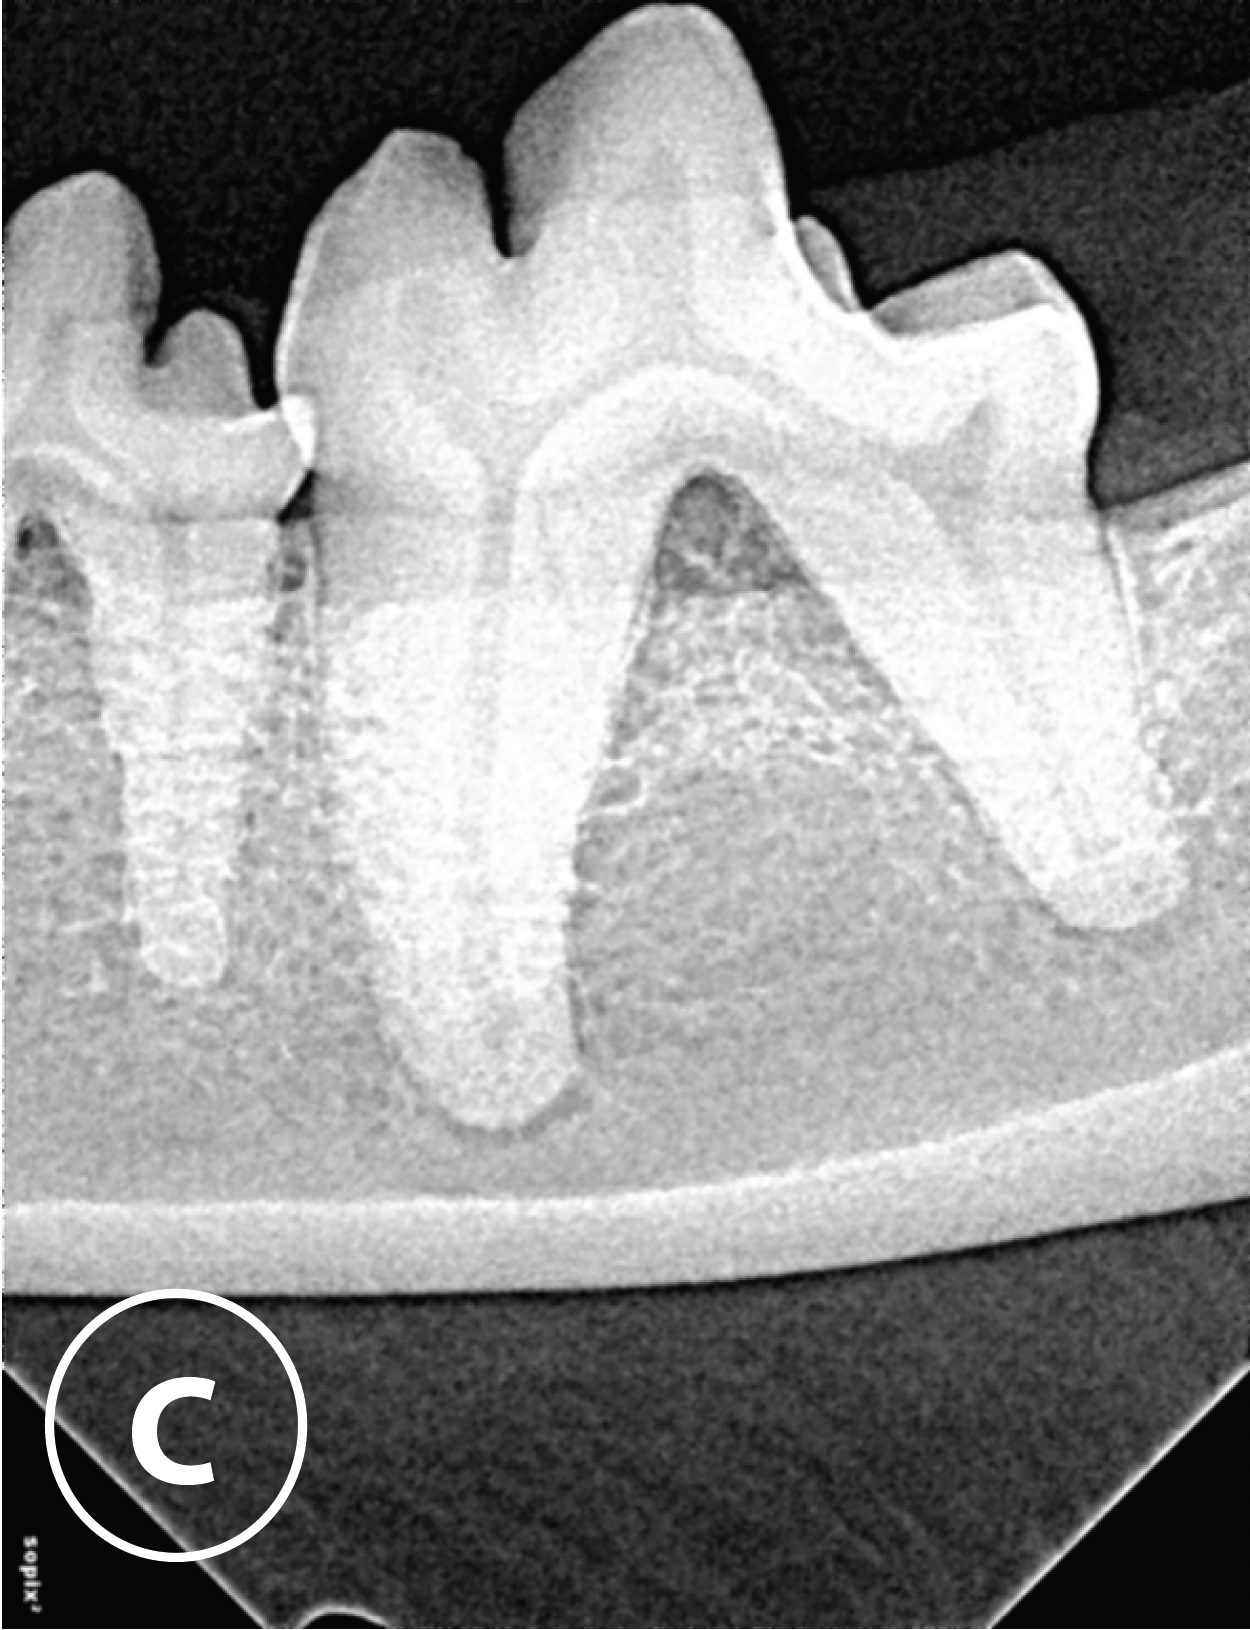

Initial radiograph

C: Radiograph 309 showing horizontal bone loss and furcation exposure.